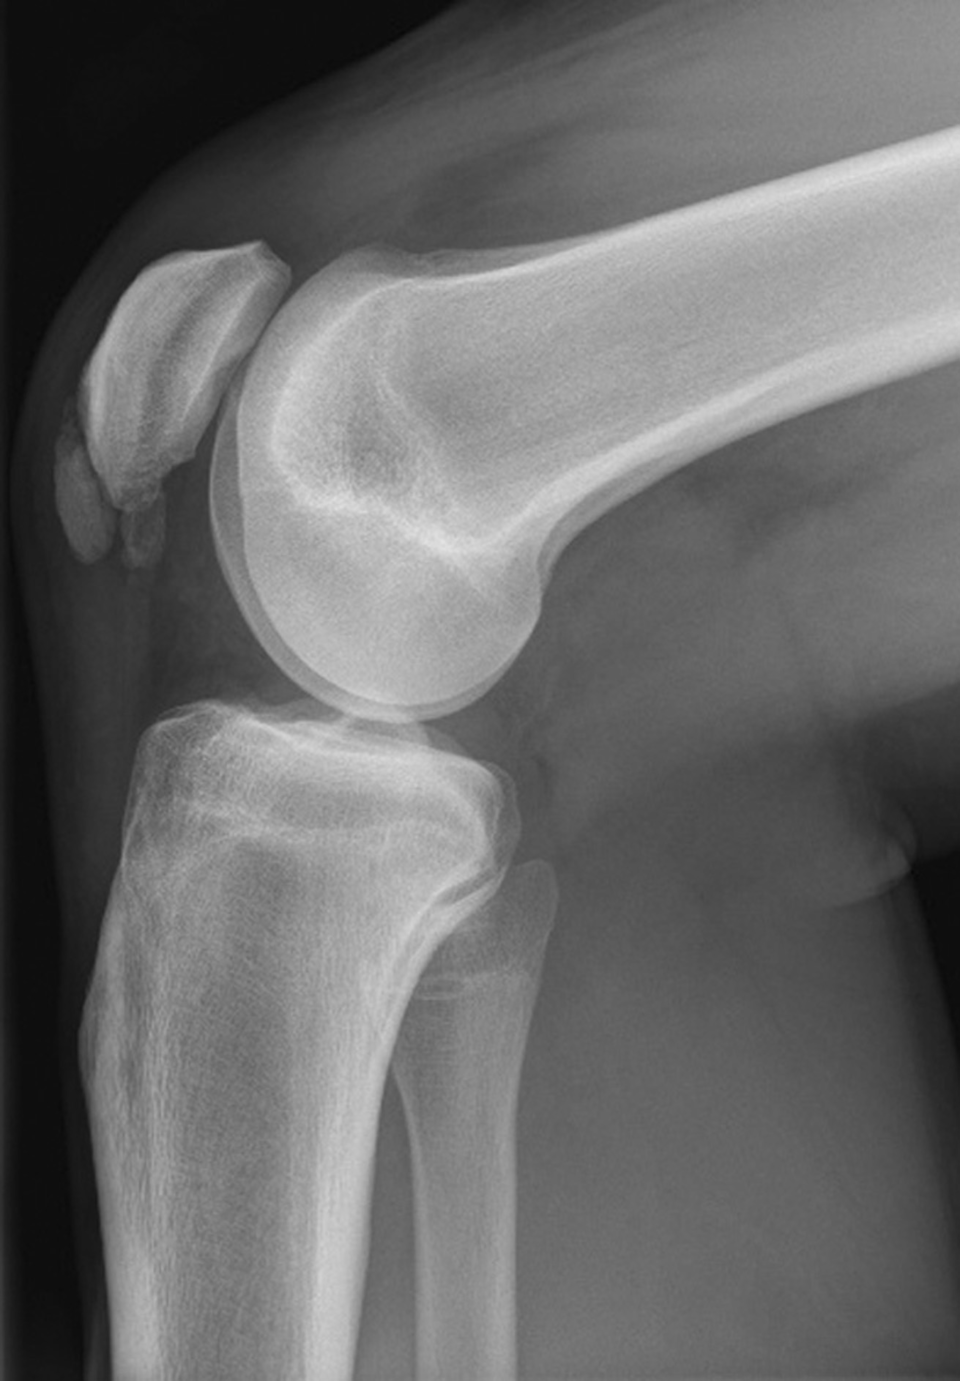

Der Morbus Blount, eine Wachstumsstörung der medialen Tibia-Epiphysenfuge, betrifft vor allem afrikanischstämmige Kinder. Der Morbus Blount, eine Wachstumsstörung der medialen Tibia-Epiphysenfuge, betrifft vor allem afrikanischstämmige Kinder. © wikimedia/Kinderradiologie Olgahospital Klinikum Stuttgart